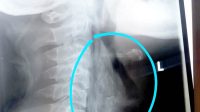

Papuyu Tersangkut di Tenggorokan Mancing Mania

Editor : Almin Hatta PARINGIN, Ikan Papuyu (Betik, Batok; red) merupakan ikan air tawar dan cukup dikenal di Indonesia, terutama […]